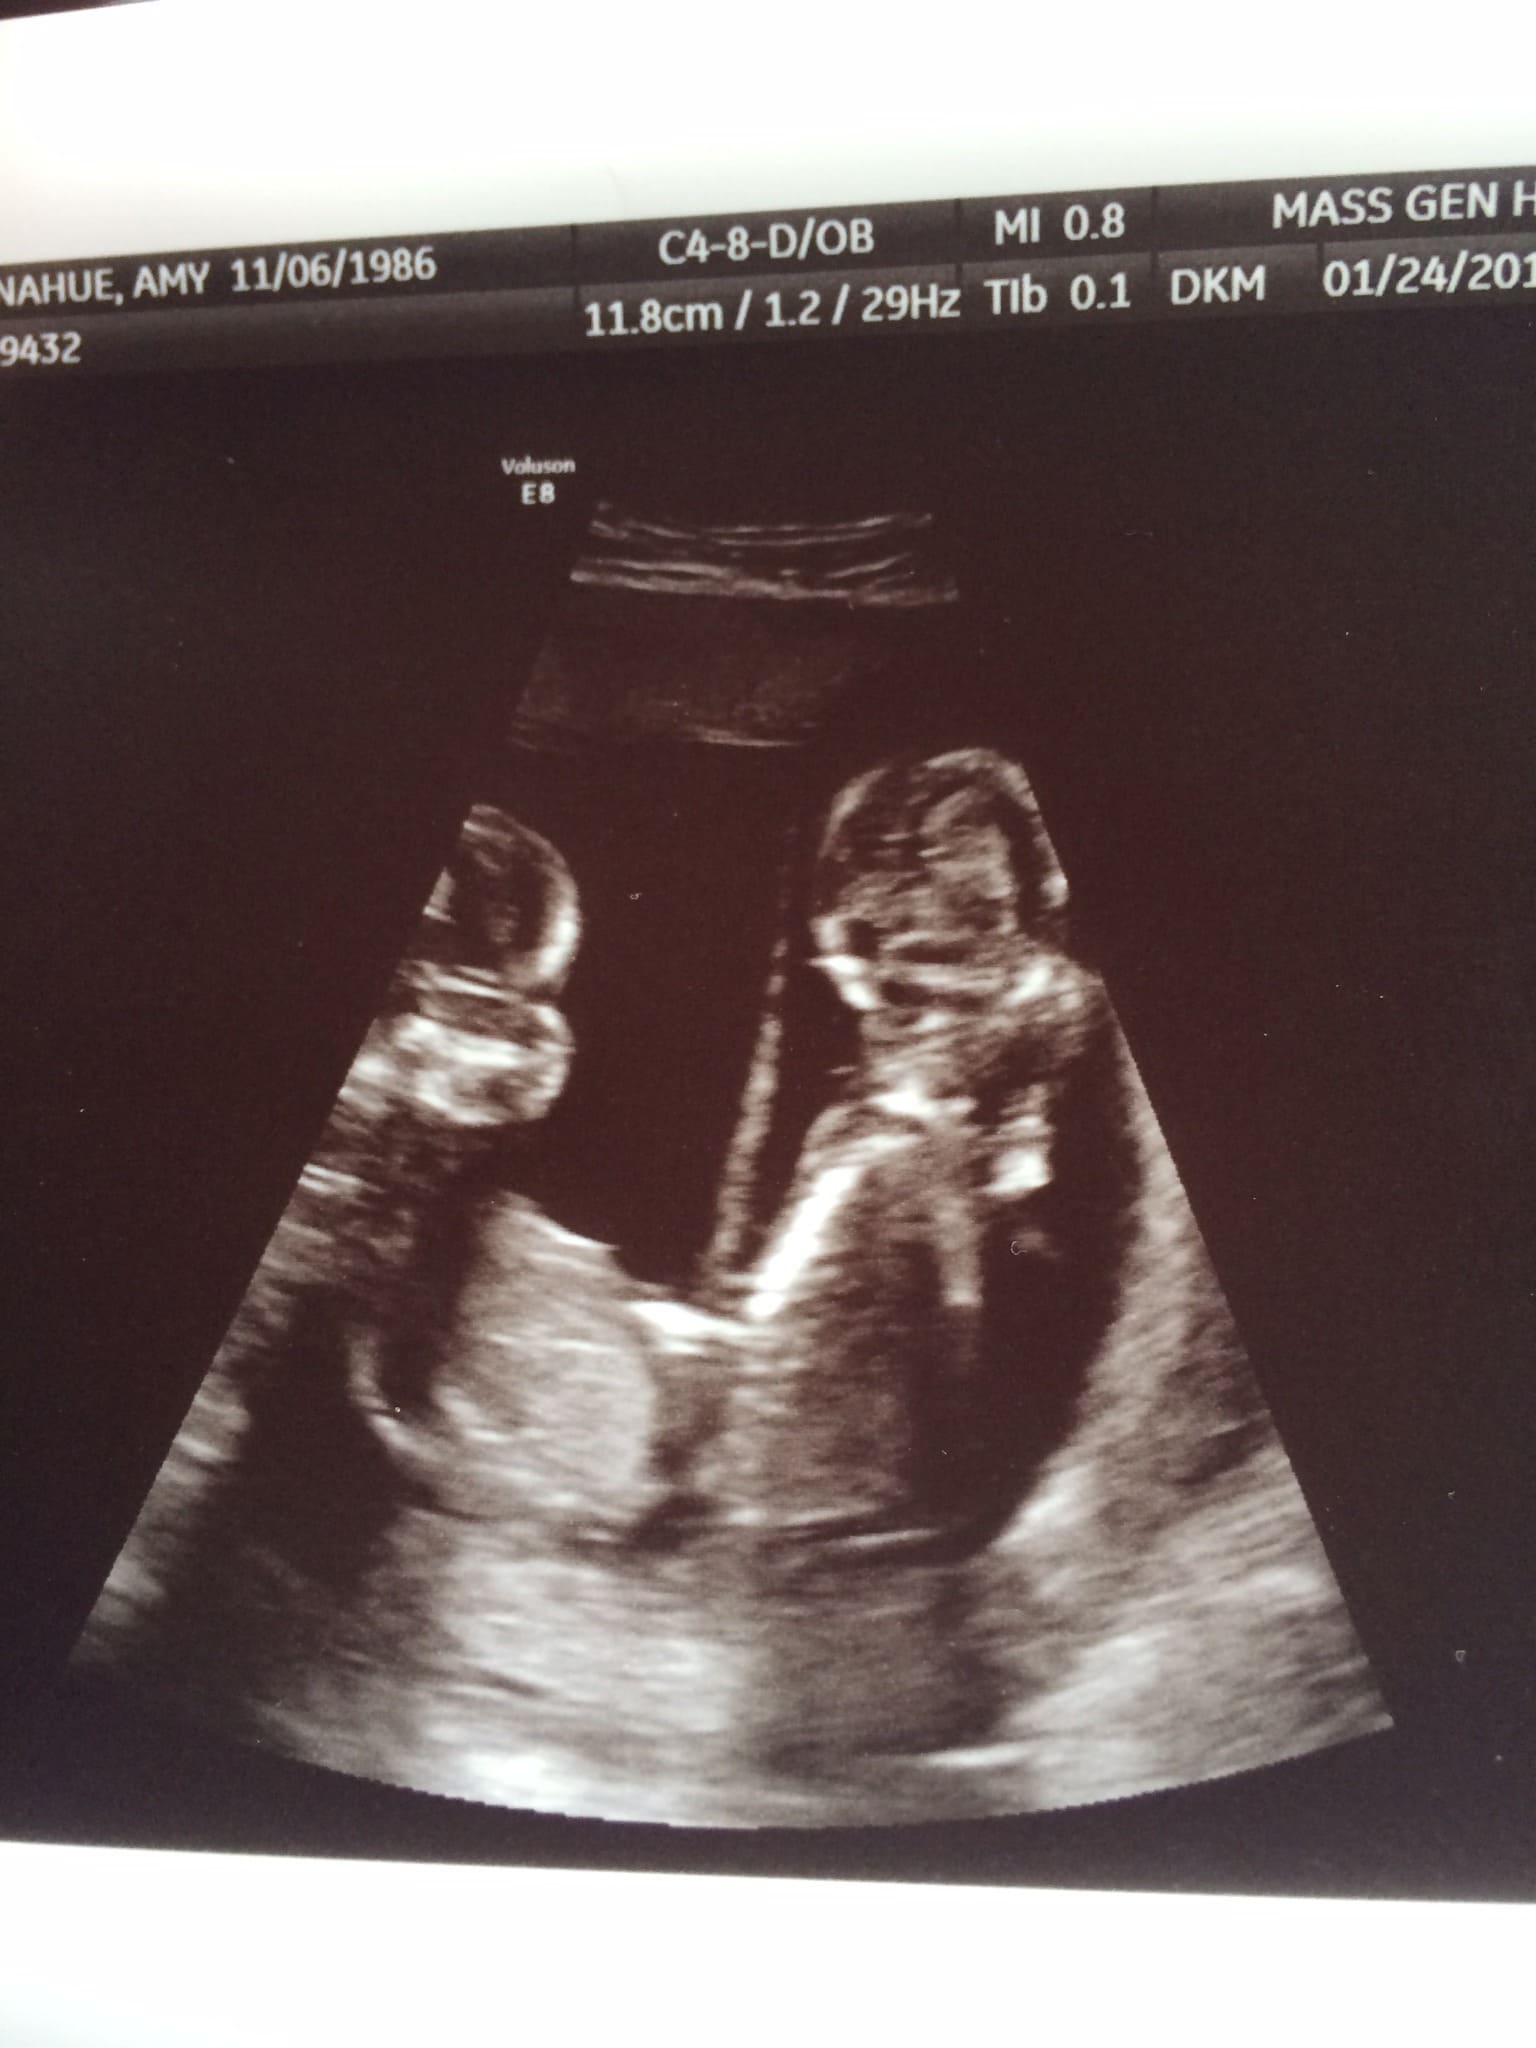

- Ultrasound Photos at 16 Weeks Pregnant With Twins

Ultrasound Photos at 16 Weeks Pregnant With Twins